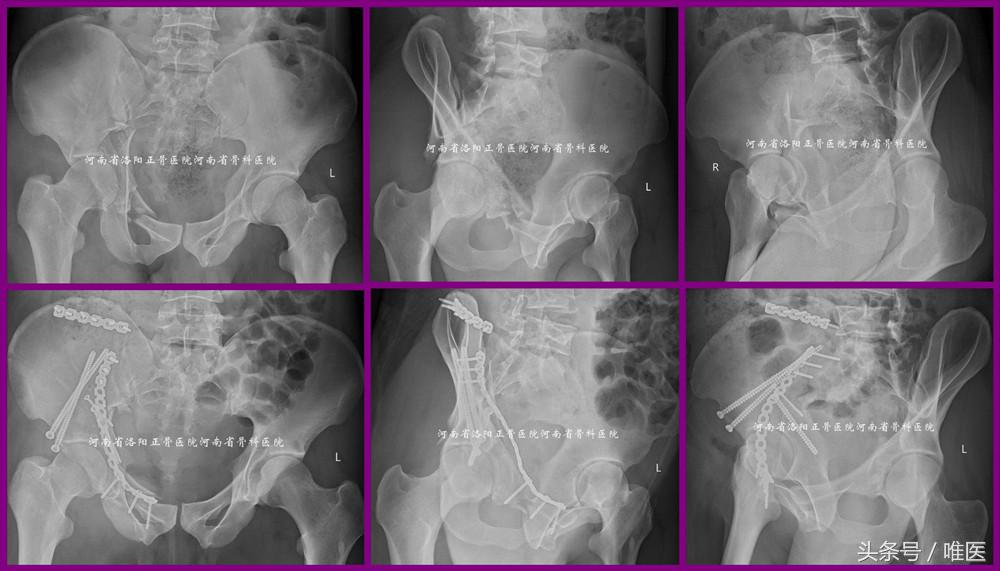

病例1:即本文第一部分所述病例。术前影像资料见图1。术后影像资料见图11。病人术后第一天即坐起活动而有效地降低了卧床并发症。此处给出开篇问题的答案。

图11. LC-II螺钉的经皮置入技术用于治疗LC-II(即OTA-61B2.3)型骨盆骨折。